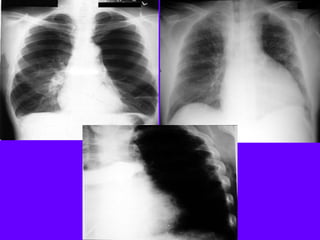

Left Upper Lobe Consolidation

Density in the left upper lung field

Loss of silhouette of left heart margin

Density in the projection of LUL in lateral view

Air bronchogram in PA view

No significant loss of lung volume